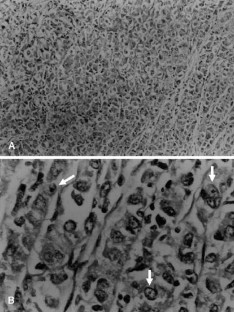

Fig. 3 A